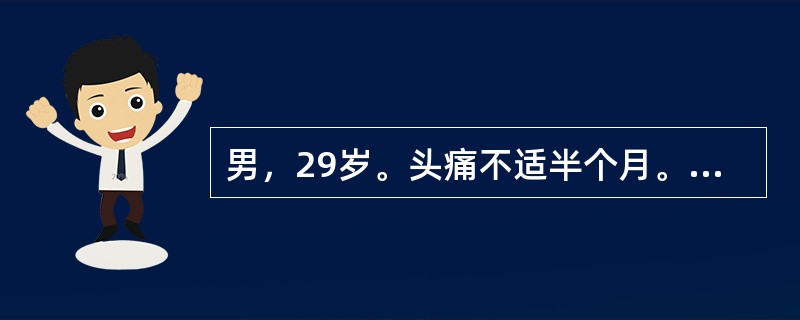

男,29岁。头痛不适半个月。MRI扫描如图示。据此可作出以下最可能的诊断是()

A.脑转移瘤

B.脑囊虫病

C.脑弓形虫病

D.脑脓肿

E.未见异常

[单选题]男,29岁,头痛不适半个月,MRI扫描如图,最可能的诊断是()A.脑转移瘤B.脑囊虫病C.脑弓形虫病D.脑脓肿E.未见异常

[单选题]男,29岁。头痛不适半个月。MRI扫描如图示。据此可作出以下最可能的诊断是()A . 脑转移瘤B . 脑囊虫病C . 脑弓形虫病D . 脑脓肿E . 未见异常

[单选题]男,29岁。头痛不适半个月。MRI扫描如图示。据此可作出以下最可能的诊断是()A .脑转移瘤B .脑囊虫病C .脑弓形虫病D .脑脓肿E .未见异常

男,29岁,头痛不适半个月,MRI扫描如图,最可能的诊断是()

[单选题]男,29岁,头痛不适半个月,MRI扫描如图,最可能的诊断是()A . 脑转移瘤B . 脑囊虫病C . 脑弓形虫病D . 脑脓肿E . 未见异常

男,29岁,头痛不适半个月,MRI扫描如图,最可能的诊断是()

[单选题]男,29岁,头痛不适半个月,MRI扫描如图,最可能的诊断是()A .脑转移瘤B .脑囊虫病C .脑弓形虫病D .脑脓肿E .未见异常